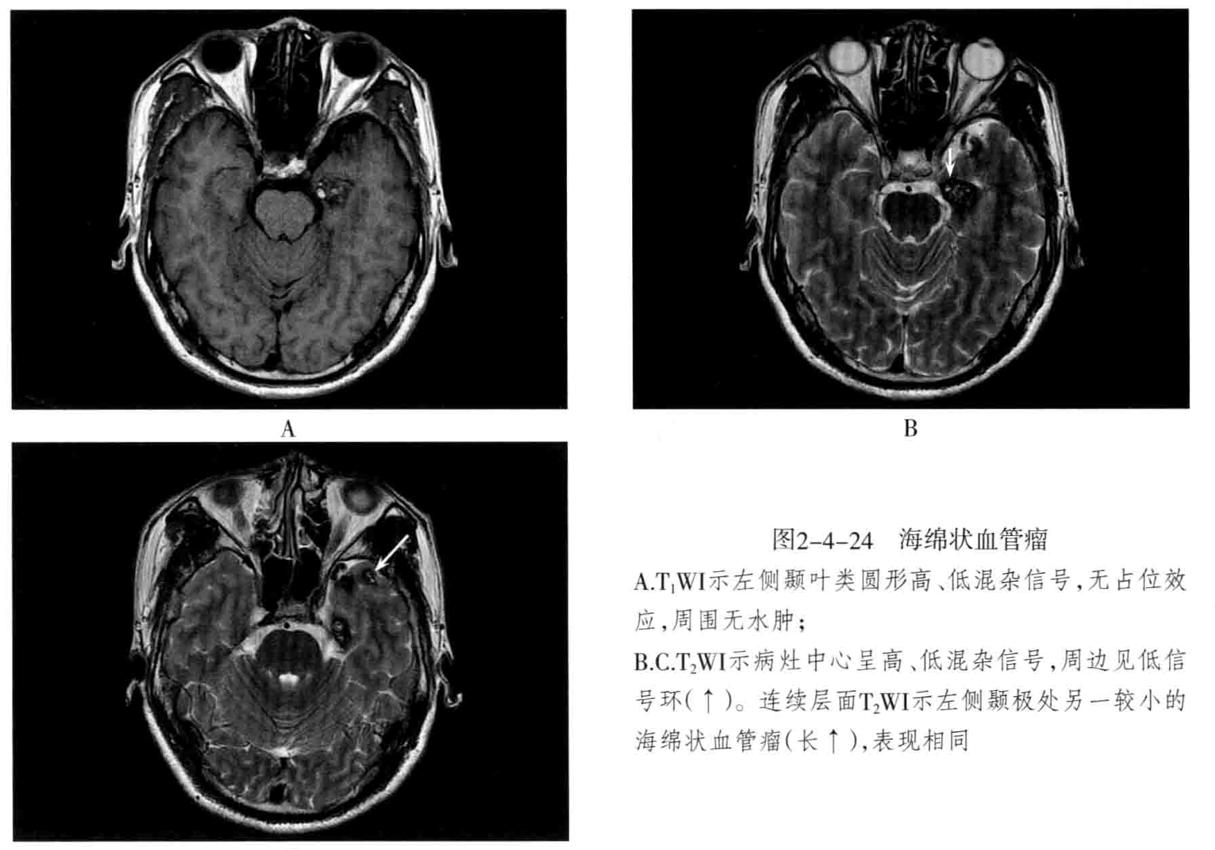

- 海绵状血管瘤 : 病变主要由不规则、大小不等的薄壁海绵状血窦组成,其间有增生的胶质组织,没有正常的神经组织,可反复少量出血,常有不同程度的钙化和含铁血黄素沉着。可发生于脑内(常见于大脑半球各叶)、脑外(常见于颅底)。常无任何症状,或表现为癫痫等。

- CT检查:类圆形高密度或稍高密度病灶,边界清楚,病灶内密度多数不均匀,常伴有明显钙化,呈斑点状或斑块状。病灶周围一般无水肿。增强扫描出现不同程度强化。

- MRI检查:T1WI多呈高信号、稍高信号或混杂信号,T2WI上呈高、低混杂信号,典型者呈“爆米花”状,境界清楚,病灶周围有含铁血黄素沉积,T2WI是表现为低信号环。病灶内及周边无流空血管影。病灶无占位效应,周围脑组织无水肿。大量出血时,表现为病灶短期明显增大,可有占位效应。增强后脑内者病灶可轻度强化,亦可无强化。脑外者多于颅底鞍旁,T1WI低信号,T2WI明显高信号,边界清楚,增强后明显强化且强化均匀。